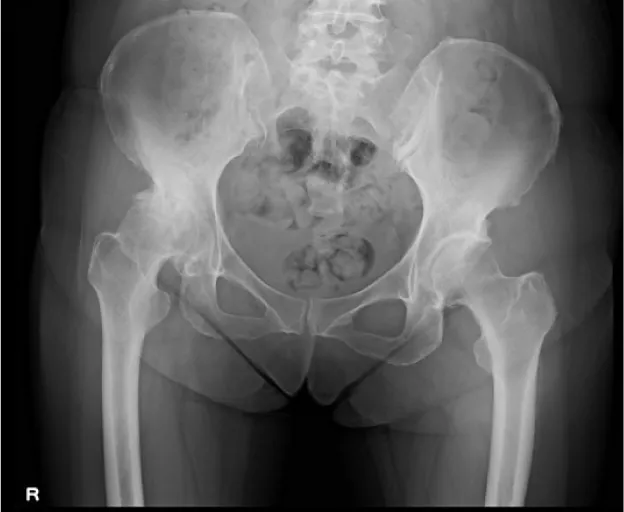

• O脚膝 術前

人工股関節置換術

主に変形性股関節症に対して行われる手術です。人工関節の中では、膝関節に次いで多く、日本で年間約7万件行われていると言われています。人工関節材料や手術方法が目覚しく発展し、耐用年数は大幅に伸びています。

現在は手術後20年経過しても、約80%の患者さんで入れ替えが不要と言われています。当院では膝関節同様、手術前に撮影したCTを元に、3次元的な術前計画を行い、個々の骨形態に対し適格な設置位置を確認しています。さらに術中簡易ナビゲーションを使用し、より正確な設置ができるよう心がけています。人工股関節手術は骨を扱う手術のため、術中に骨から出血を起こします。

• 術前レントゲン